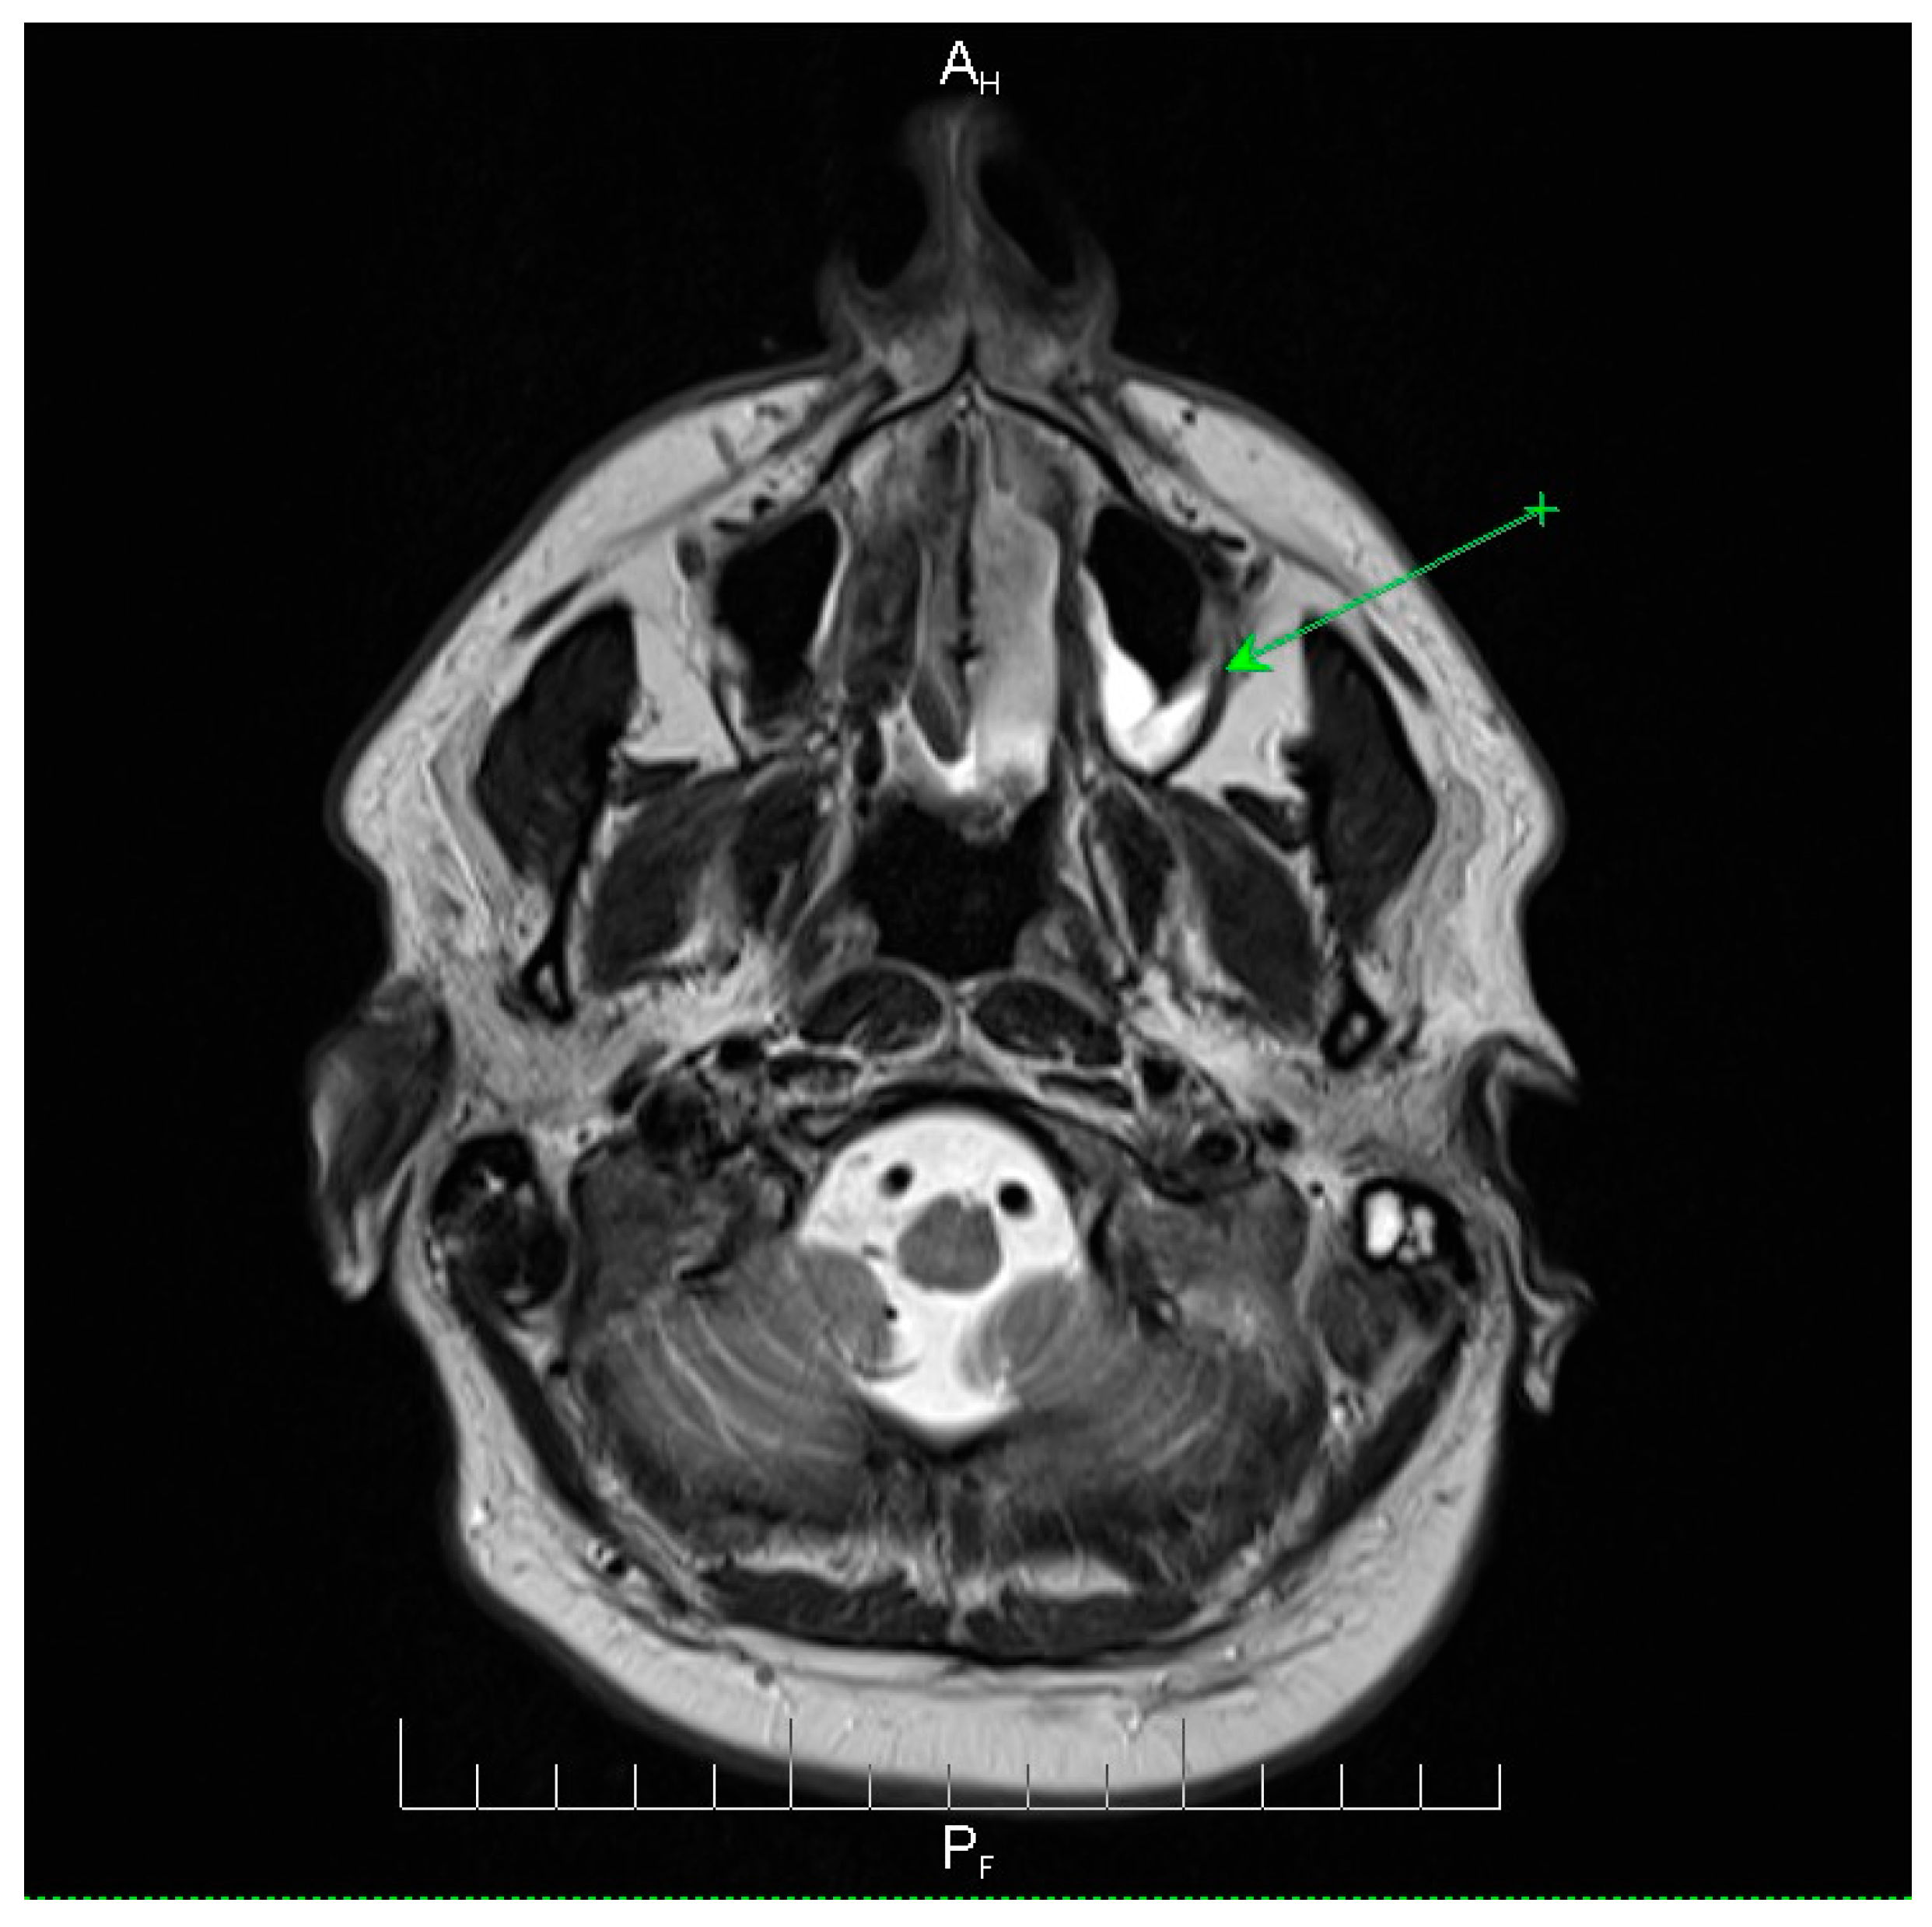

Neuroimaging revealed mild ethmoidal/sphenoidal sinus opacification and left mastoid air cell involvement without evidence of parenchymal lesions or venous sinus thrombosis (Figure 1, Figure 2 and Figure 3). Coronal and axial T2-weighted MRI sequences revealed para-fluid collections within the left mastoid air cells extending toward Citelli’s angle (Figure 1, Figure 2 and Figure 3), consistent with an otogenic focus and a possible contiguous route for intracranial spread.

Figure 3.

Axial T2-weighted MRI scan demonstrating the post-septoturbinoplasty reduction status on the right. Mild inflammatory changes were observed in the mucosa of the maxillary sinuses, predominantly on the left side, with less pronounced involvement of the ethmoidal cell system. No evidence of acute intracranial pathology or parenchymal lesions was observed. These findings indicate residual postoperative changes and mild sinonasal inflammation, providing context for the patient’s clinical presentation and helping to differentiate postoperative alterations from active infectious processes. AH = anterior-head. PF = posterior- foot. Axial T2-weighted MRI scan demonstrating the post-septoturbinoplasty reduction status on the right. The green arrow indicates a focal area of mucosal thickening and fluid signal within the left maxillary sinus, consistent with mild inflammatory changes, with less pronounced involvement of the ethmoidal cell system. No evidence of acute intracranial pathology or parenchymal lesions was observed. These findings indicate residual postoperative changes and mild sinonasal inflammation, providing context for the patient’s clinical presentation and helping to differentiate postoperative alterations from active infectious processes.